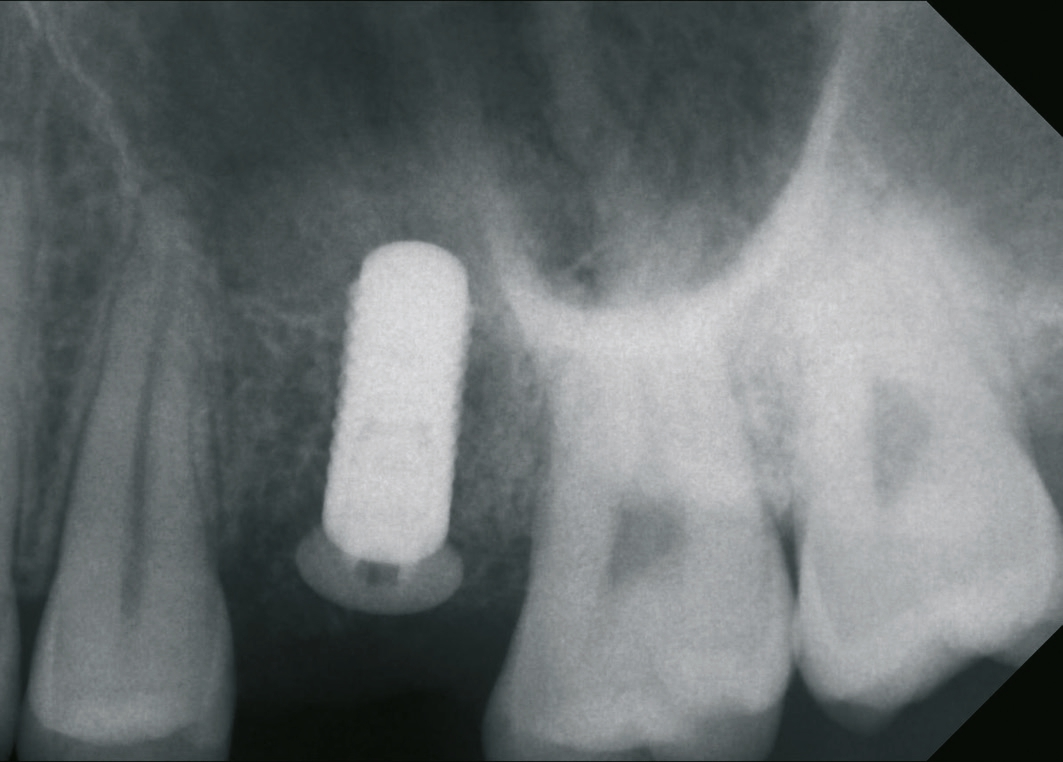

Ein 21-jähriger Patient stellte sich mit einer Perkussionsempfindlichkeit in regio 26 vor. Die klinische Untersuchung zeigte einen tiefzerstörten Zahn 26, dessen gesamte palatinale Wand tief fraktruiert war. Die Frakturgrenze verlief dabei weit unter dem palatinalen Zahnfleischrand (Abb. 1). Nach Erstellung eines Orthopantomogramms und einer radiologischen Einzelzahnbildaufnahme war eine längliche Verschattung am Apex der palatinalen Wurzel des Zahn 26 zu erkennen (Abb. 2), die den Verdacht einer überinstrumentierten Wurzelkanalaufbereitung der palatinalen Wurzel und einer Überstopfung des Füllmaterials bestätigte (Abb. 3). Nach konservierender Theapie wurde die Indikationsstellung für die Extraktion des Zahnes 26 mit einer Sofortimplantation gestellt. Der Periodontal-Screening-Index wies in allen Sextanten Grad 2 auf. Es folgte die Erstellung einer dreidimensionalen Röntgenaufnahme (Orthophos XG 3D, Dentsply Sirona, Bensheim) zur virtuellen Planung der Implantatposition. Die operative Planung erfolgte in der Planungssoftware coDiagnostiX 9.5 (dental wings, Montreal, Kanada) (Abb. 4).